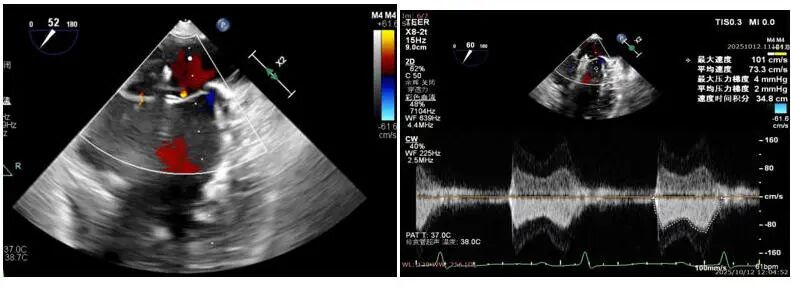

患者女性,72岁,反复心悸、胸闷多年,既往曾在外院接受房颤射频消融,但术后再次复发。入院后检查发现:房颤合并中重度二尖瓣反流,且瓣口面积仅4.3cm²,病情复杂、风险极高。经多学科团队联合评估,本次手术中,团队通过三维标测系统精准定位心律失常触发点,并以脉冲消融完成心房电活动重构。消融后心律即刻恢复窦性节律,体现了PFA在病例中快速、精准、微创的独特优势。与传统射频消融相比,脉冲消融显著减少肺静脉狭窄及食管损伤风险,术后房颤复发率更低,为房颤患者提供了更优的治疗方案。针对患者的中重度二尖瓣反流,手术团队在精准经食道超声导航下完成TEER瓣膜修复。瓣叶精准对合后,反流明显减少,跨瓣压差维持在理想水平,术后心功能显著改善。

在瓣口面积偏小仅有4.3cm²的情况下,决定术中在2区植入一枚SW0609型号DragonFly™二尖瓣夹解决反流问题,术中用到DragonFly™二尖瓣夹前后瓣叶独立捕获功能,实现了对病变瓣叶的精准定位与捕获。术中房间隔穿刺高度3.8cm,夹闭后L侧微量反流,释放后反流未明显增加,跨瓣压差2mmHg